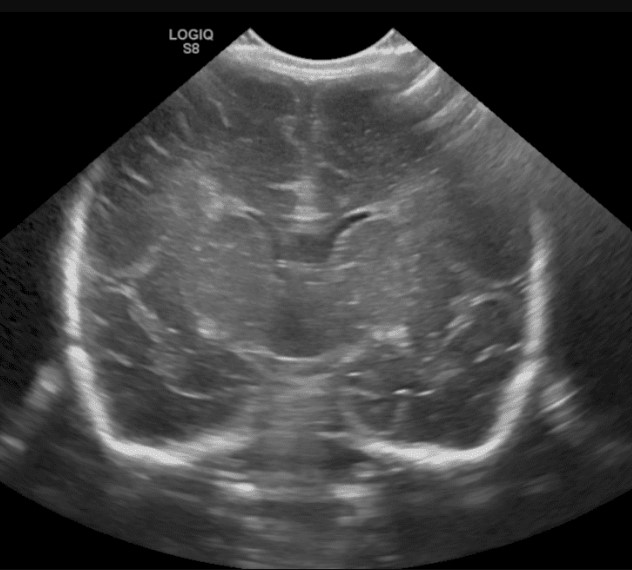

Ultrason (US) pratik ve hızlı bir görüntüleme yöntemidir. Ses dalgalarını kullanarak yapıldığından bilinen bir yan etkisi yoktur, bu nedenle gebeliklerde sık tercih edilen bir görüntüleme yöntemidir.

Pediatrik nörolojide kullanım alanları:

- Prematürelerde beyinde kanama ve zedelenme takibi

- Bıngıldağın açık olduğu yaşlarda:

Beyin dokusunun görüntülenmesi

Hidrosefali takibi - Tortikolis‘de SCM kasının değerlendirilmesi

Diğer görüntüleme yöntemlerine göre dokuya yönelik detay kısıtlıdır. Buna ihtiyaç olan durumlarda BT veya MR gibi testlere başvurulur.